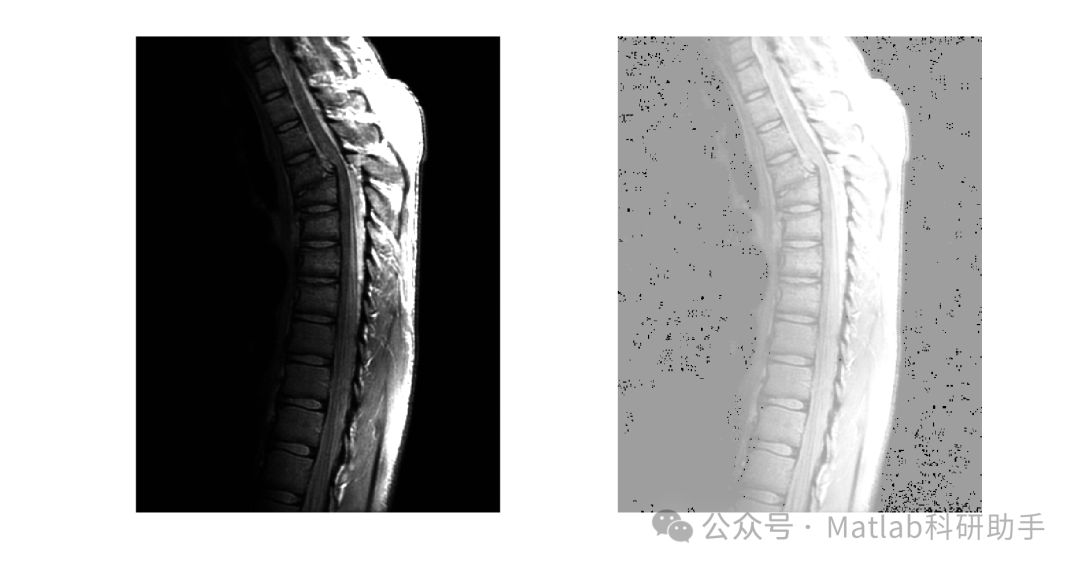

- 医学图像处理:

用于增强X光片、CT扫描、MRI图像等医学图像的对比度,帮助医生更清晰地观察病变组织。

⛳️ 运行结果